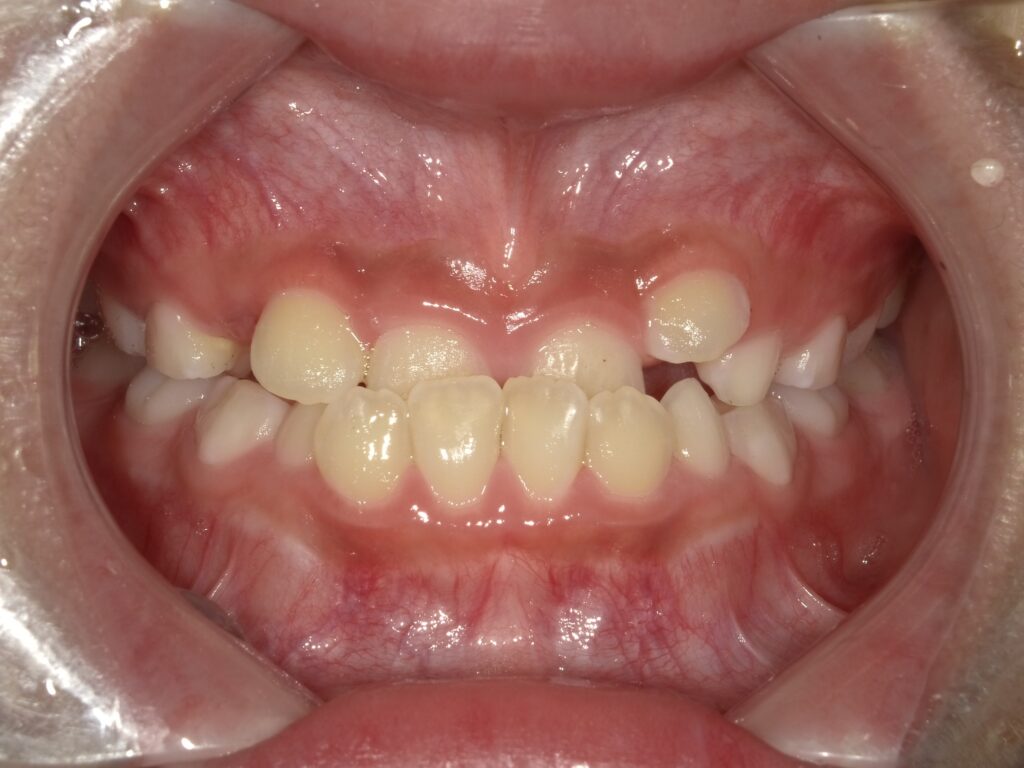

【症例】混合歯列期の反対咬合(8歳・男児)

混合歯列期に上顎の発達不足が見られ、反対咬合を呈していたため、治療介入。

上顎の成長を促すことで、骨格性の反対咬合への進行を防ぐことができました。

■ 初診時の状態

この時期はすでに上下の1番・2番・6番が萌出しており、

顎の成長コントロールが可能な重要なタイミングでした。

反対咬合を放置すると、

・ 上顎の成長が抑制される

・ 下顎が前方に成長しやすくなる

・ 将来的に骨格性の受け口へ進行する可能性

があるため、早期の1期治療を開始しました。